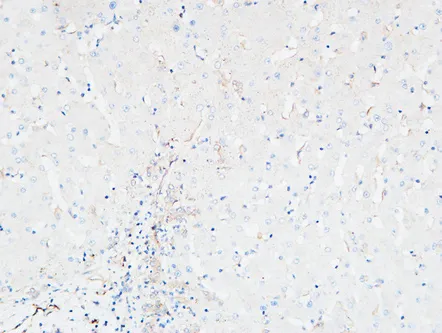

MPO Rabbit Polyclonal Antibody

Cat: APRab14056

Size1:50μl Price1:$118

Size2:100μl Price2:$220

Size3:500μl Price3:$980